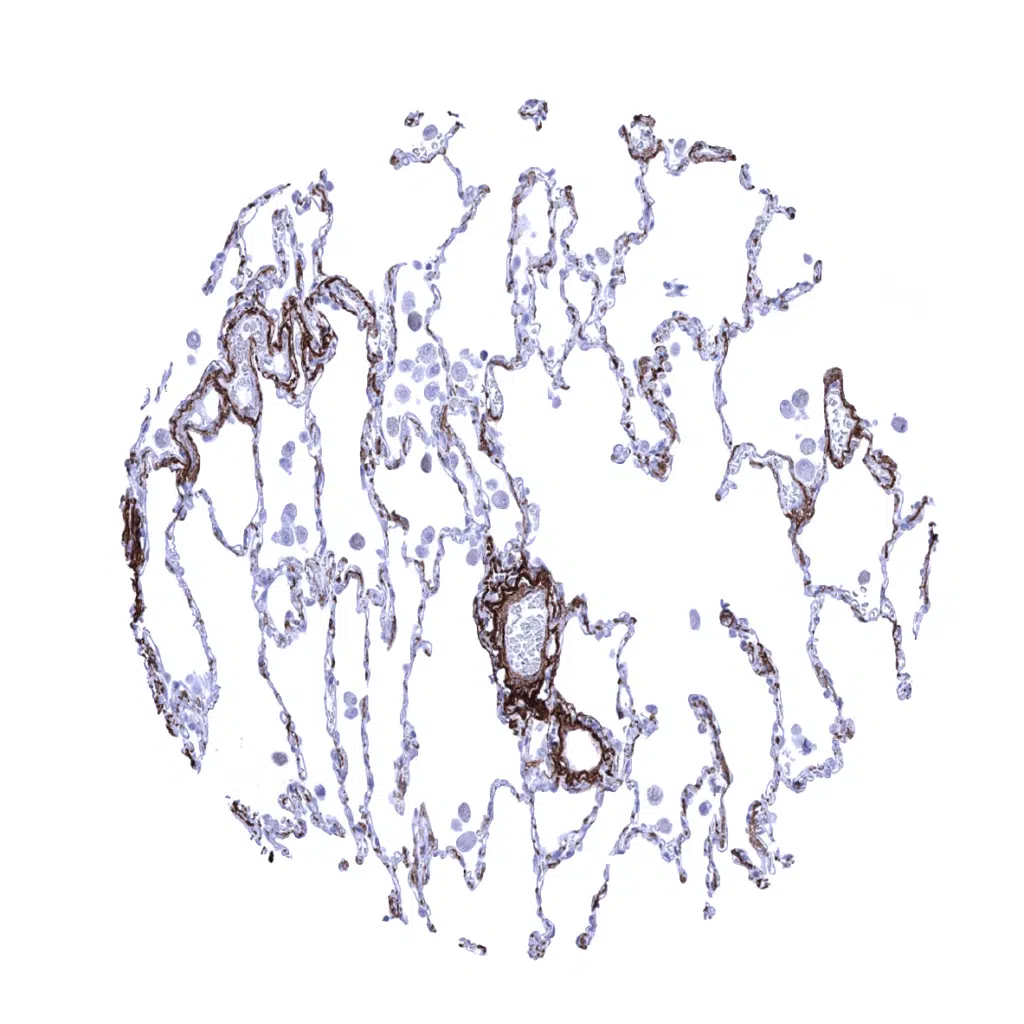

Lung – High content of elastin fibres in lung tissue.